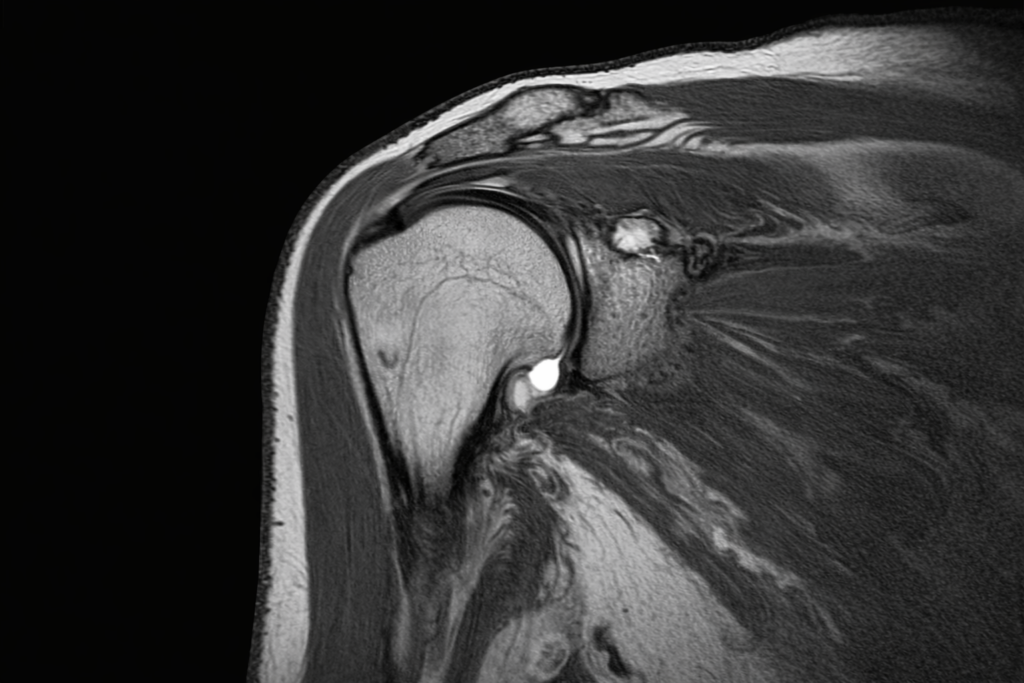

4. MRI

Recommended when symptoms persist or when surgical planning is needed.

Shows:

- AC joint degeneration

- Bone marrow oedema

- Ligament tears

- Associated rotator cuff pathology